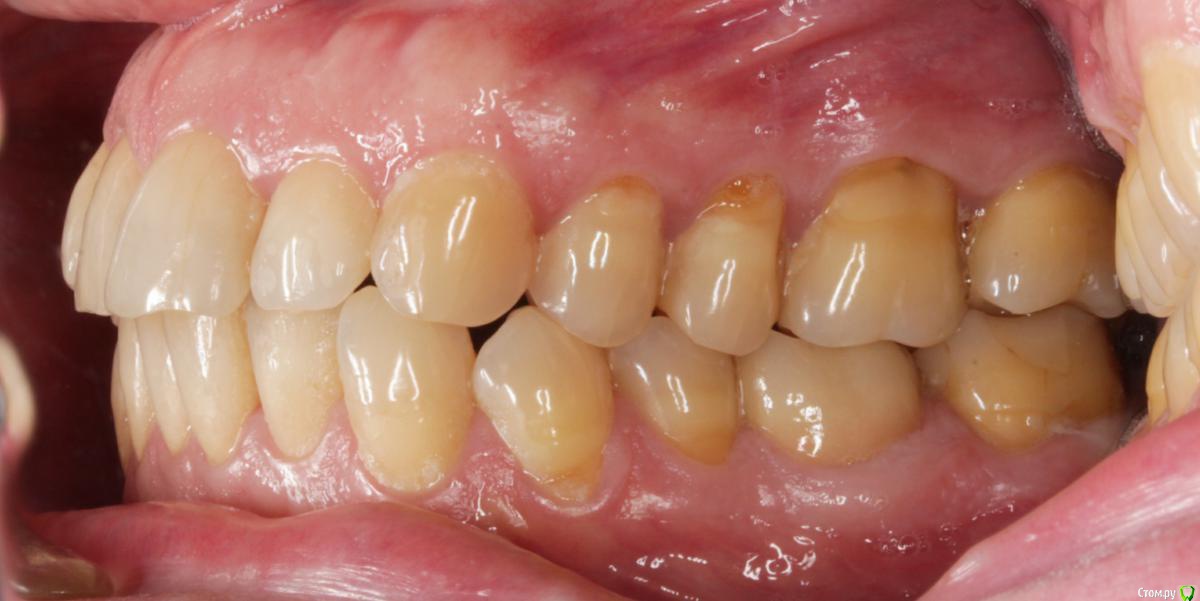

Dmitry DK Опубликовано 29 августа, 2019 Поделиться Опубликовано 29 августа, 2019 Добрый день всем! Случай достаточно заурядный, но возможно кому-то будет интересно. Результат - 2 года спустя 13 Ссылка на комментарий